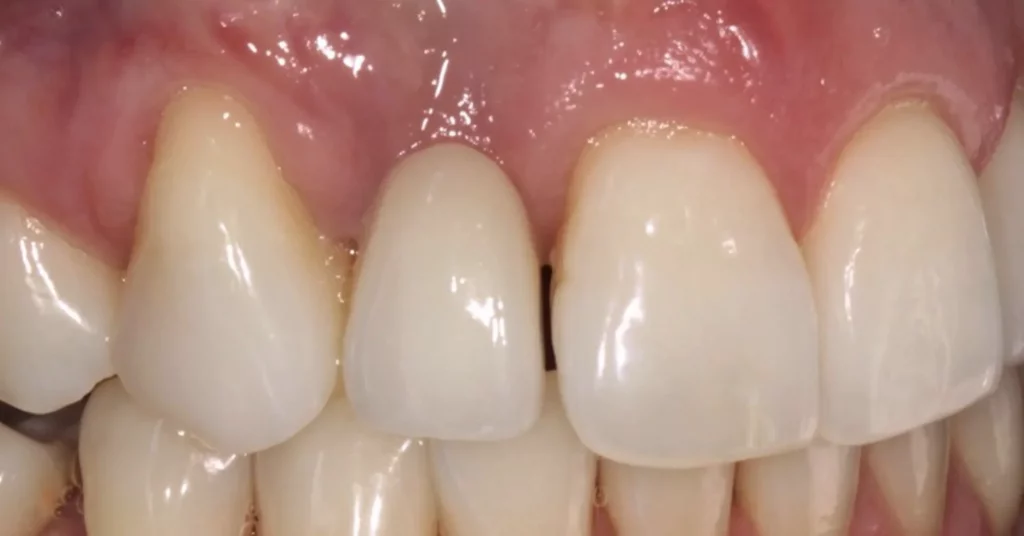

This lady attended Gentle after a previous implant had not worked. In the left photo below is a temporary bridge that kept falling out, which was frustrating for the patient, so she wanted to try again with implant treatment. Moreover, when she smiled, the adjacent eye tooth had an exposed root, so it looked too long. At the same time as placing gum around the implant, a gum graft was placed to cover the exposed eye tooth root. This improves the overall aesthetic outcome for the patient. Below on the right you can see how we took time to rebuild the bone and gum in the first phase of treatment, which gave the implant a solid foundation to sit in.

The implant was placed into the bone, under the gum, and a white post was chosen to fit into the implant to maximise the final crown’s appearance. The after photo was taken 5 years after the implant was placed and shows how nicely the work is performing.